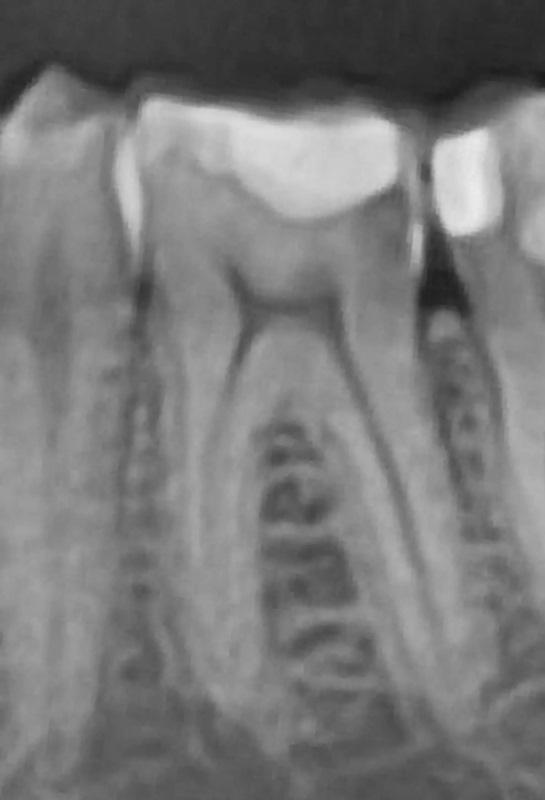

Лечение было сосредоточено на первом моляре нижней челюсти с использованием существующих композитных реставраций I и V классов (фото 1). Состояние зуба протекало бессимптомно, и фриз-тест показал нормальную реакцию. Дистальное кариозное поражение, которое не было клинически заметно, было впервые заподозрено во время планового обследования, и его протяженность была четко определена на панорамной рентгенограмме (фото 2).

Фото 2: Панорамная рентгенограмма, показывающая дистальное кариозное поражение.